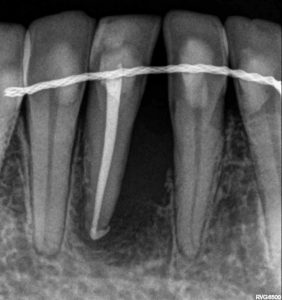

Objetivos periodontales: Regeneración osea guiada con bioss collagen y emdogain.

- Eliminar tejido necrótico. Regeneración periodontal cemento, ligamento y hueso

- Mejora de la estabilidad y soporte óseo

- Estabilidad periodontal y reducción de la movilidad

R.A.R. Profundo suave intraquirúrgico

Aplicación protocolo emdogain

Regeneración ósea guiada con membrana de colageno creos de Nobel Biocare y relleno óseo mediante BIOSS Collagene de INIBSA, con elementos de fijación a la membrana para R.O.G.

Fotografías del proceso: